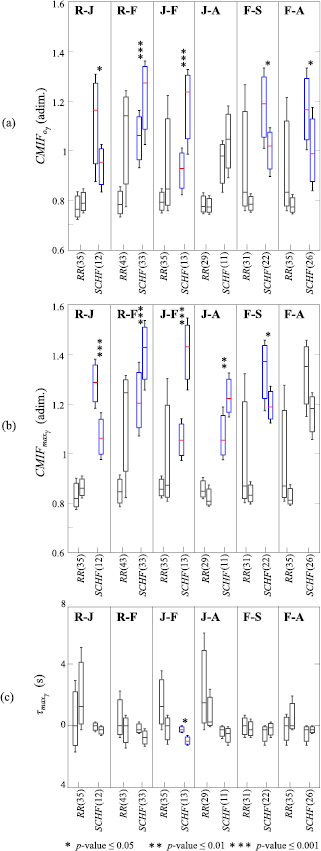

3.3. CMIF-based measures

All parameters derived from the CMIF have been evaluated, however, only those that revealed statistically significant differences for their ability to discriminate between pair of emotions are shown in figure 5. In this figure, boxplots are shown in terms of median and interquartile ranges as first and third quartile:  (figure 5(a);

(figure 5(a);  (figure 5(b) and

(figure 5(b) and  (figure 5(c) for the coupling between each signal

(figure 5(c) for the coupling between each signal  = {RR, SCHF} and r(t).

= {RR, SCHF} and r(t).

Figure 5. Boxplots of the parameters derived from the CMIF: (a)  , (b)

, (b)  and (c)

and (c)  , for the coupling between each of the signals

, for the coupling between each of the signals  = {RR, SCHF} and r(t) and all emotion conditions studied with statistically significant differences: relax and joy (R-J), relax and fear (R-F), joy and fear (J-F), joy and anger (J-A), fear and sadness (F-S) and fear and anger (F-A). Statistical significance is denoted by: * for p -value

= {RR, SCHF} and r(t) and all emotion conditions studied with statistically significant differences: relax and joy (R-J), relax and fear (R-F), joy and fear (J-F), joy and anger (J-A), fear and sadness (F-S) and fear and anger (F-A). Statistical significance is denoted by: * for p -value  0.05, ** for p -value

0.05, ** for p -value  0.01 and *** for p -value

0.01 and *** for p -value  0.001, all with sensitivity, specificity and accuracy

0.001, all with sensitivity, specificity and accuracy  70% and AUC index

70% and AUC index  0.70. In each x-axis the number of the analysed subjects is indicated in parentheses.

0.70. In each x-axis the number of the analysed subjects is indicated in parentheses.

Download figure:

Standard image High-resolution imageIn table 5, p -value, AUC and accuracy values are remarked in bold type for those CMIF-based parameters that revealed statistically significant differences between the emotional states studied. The presented elicited conditions were those which revealed statistically significant differences.

The CMIF has been proposed to reveal non-linear cardiorespiratory interdependencies (Hoyer et al 2002), which might be altered during emotion elicitation. For example, a significant increase in the CMIF of electroencephalographic signals has been also observed in the presence of stress (Alonso et al 2015). In our study, the parameter  (figure 5(a) and the parameter

(figure 5(a) and the parameter  (figure 5(b) provide similar information, although the slight differences in the calculation of both parameter revealed that

(figure 5(b) provide similar information, although the slight differences in the calculation of both parameter revealed that  is able to discriminate with an equal or better p -value, sensitivity, specificity, accuracy and AUC index than

is able to discriminate with an equal or better p -value, sensitivity, specificity, accuracy and AUC index than  in all compared elicited states, except for fear and anger. Moreover, evaluating

in all compared elicited states, except for fear and anger. Moreover, evaluating  and

and  , it is possible to extract a similar pattern for fear presenting a greater median value than any other elicited state.

, it is possible to extract a similar pattern for fear presenting a greater median value than any other elicited state.

The time lag between  and

and  in the SCHF band was the only parameter able to distinguish between joy and fear, and it suggested less non-linear correlation between HRV and respiration during joy. A complexity reduction is observed during fear elicitation as reflected by a lower value of parameter

in the SCHF band was the only parameter able to distinguish between joy and fear, and it suggested less non-linear correlation between HRV and respiration during joy. A complexity reduction is observed during fear elicitation as reflected by a lower value of parameter  .